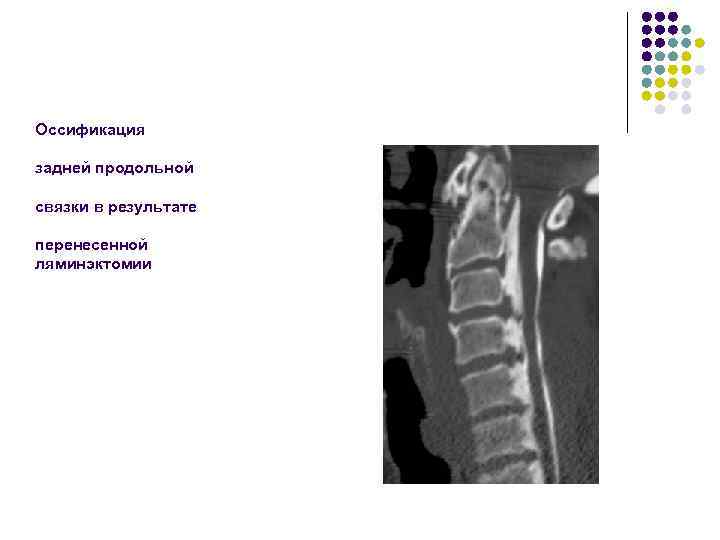

Оссификация задней продольной связки в результате перенесенной ляминэктомии